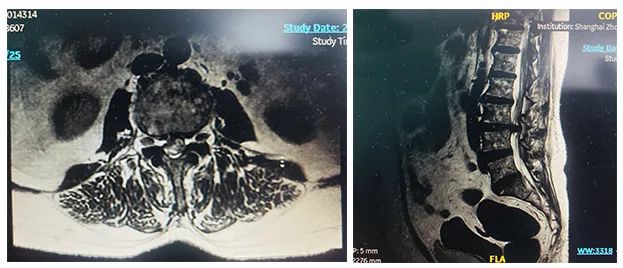

患者:女性,58岁

术式:腰骶椎椎体间融合术

患者一个月前因双侧下肢疼痛至医院就诊,诊断为腰椎间盘突出?;颊咦孕兄琳锼驼?,予以推拿牵引术,疼痛未明显缓解,到医院进一步治疗。影像诊断:L3-4椎间盘突出,椎管变窄(中央型)。

术前影像